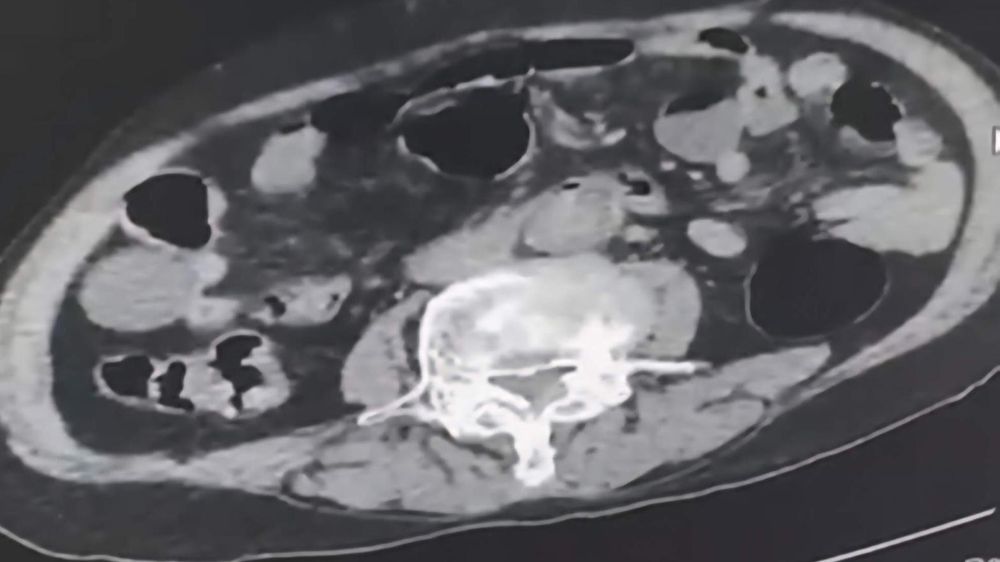

Denizli İl Emniyet Müdürlüğü Narkotik Suçlarla Mücadele Şube Müdürlüğü tarafından uyuşturucu madde ticaretinin önlenmesine yönelik yapılan çalışmalar kapsamında şehir dışından Denizli’ye uyuşturucu sokmak isteyen 2 yabancı uyruklu şahıs takibe takıldı. Takip sonrasında Denizli’de malları teslim edeceği kişi ile buluştukları esnada düzenlene operasyonla 3 şahıs gözaltına alındı. Gözaltına alınan şüpheliler üzerinde yapılan incelemelerde yabancı uyruklu bir şüphelinin uyuşturucu maddeyi cinsel organında taşıdığı belirlendi. Şüphelilerin üzerlerinde ve adreslerinden yapılan aramalarda 6 parça halinde 145 gram metamfetamin maddesi, 260 gram sıvı halde sentetik ecza maddesi ele geçirildi.